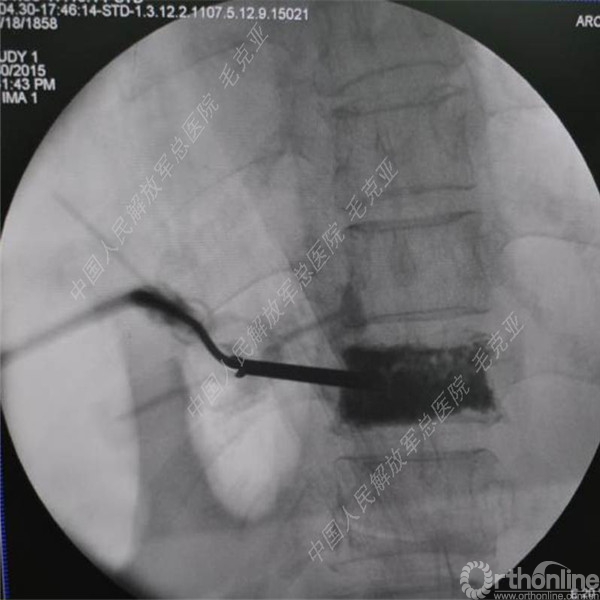

导语:随着社会老龄化的不断加速,骨质疏松性椎体压缩骨折作为一种普遍存在的老年骨科疾病已经成为现今骨科界的一个热点话题。传统的保守疗法治疗效果不佳,而现有的椎体增强技术又具有多种风险和缺陷。针对这种现状,中国人民解放军总医院毛克亚教授提供了一种新的解决方法。